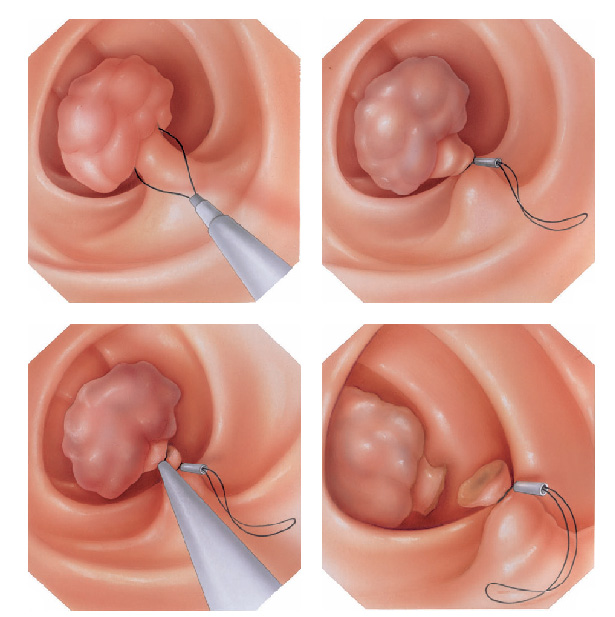

O que é a polipectomia?

A polipectomia é a remoção completa de um pólipo permitindo assim o diagnóstico exato e muitas vezes a cura do próprio problema. Existem várias técnicas para a realização do procedimento que dependem do tamanho e do tipo de pólipo a ser ressecado.

Polipectomia com alça diatérmica

Pólipos maiores necessitam ser removidos com alça e corrente de cauterização. Este procedimento permite cortar a base do pólipo e ao mesmo tempo coagular o local para evitar sangramentos.

Porém alguns pólipos possuem a base (pedículo) largo onde passam vasos calibrosos e por isto tem risco aumentado de sangramento na retirada mesmo usando a corrente de coagulação.

Nestes casos algumas medidas podem ser realizadas para diminuir o risco de sangramento:

Injeção de adrenalina na base do pólipo

Colocação de um laço na base do pólipo para estrangular o pedículo

Alguns pólipos são tão grandes que não podem ser removidos inteiros. Nestes casos o pólipo é retirado em pedaços para poder garantir a sua remoção completa.

Alguns pólipos não possuem a base alongada (pedículo), estes são chamados de pólipos sésseis. A remoção destes pólipos possui risco maior de perfuração do órgão pois como são planos ficam muito próximos da parede externa do órgão.

Mucosectomia

Para diminuir este risco, injeta-se com um uma agulha uma solução abaixo do pólipo para que ele levante e fique mais longe da parede do órgão. Após isto passa-se a alça diatérmica e realiza-se o

procedimento de polipectomia.

Tatuagem endoscópica

Nos casos onde existe a necessidade de revisão posterior do local onde foi feito o procedimento, seja por endoscopia ou por cirurgia, pode-se realizar a injeção de tinta na parede do órgão ficando assim esta região marcada permanentemente. Este procedimento é indolor e não leva a nenhum tipo de lesão do órgão marcado.